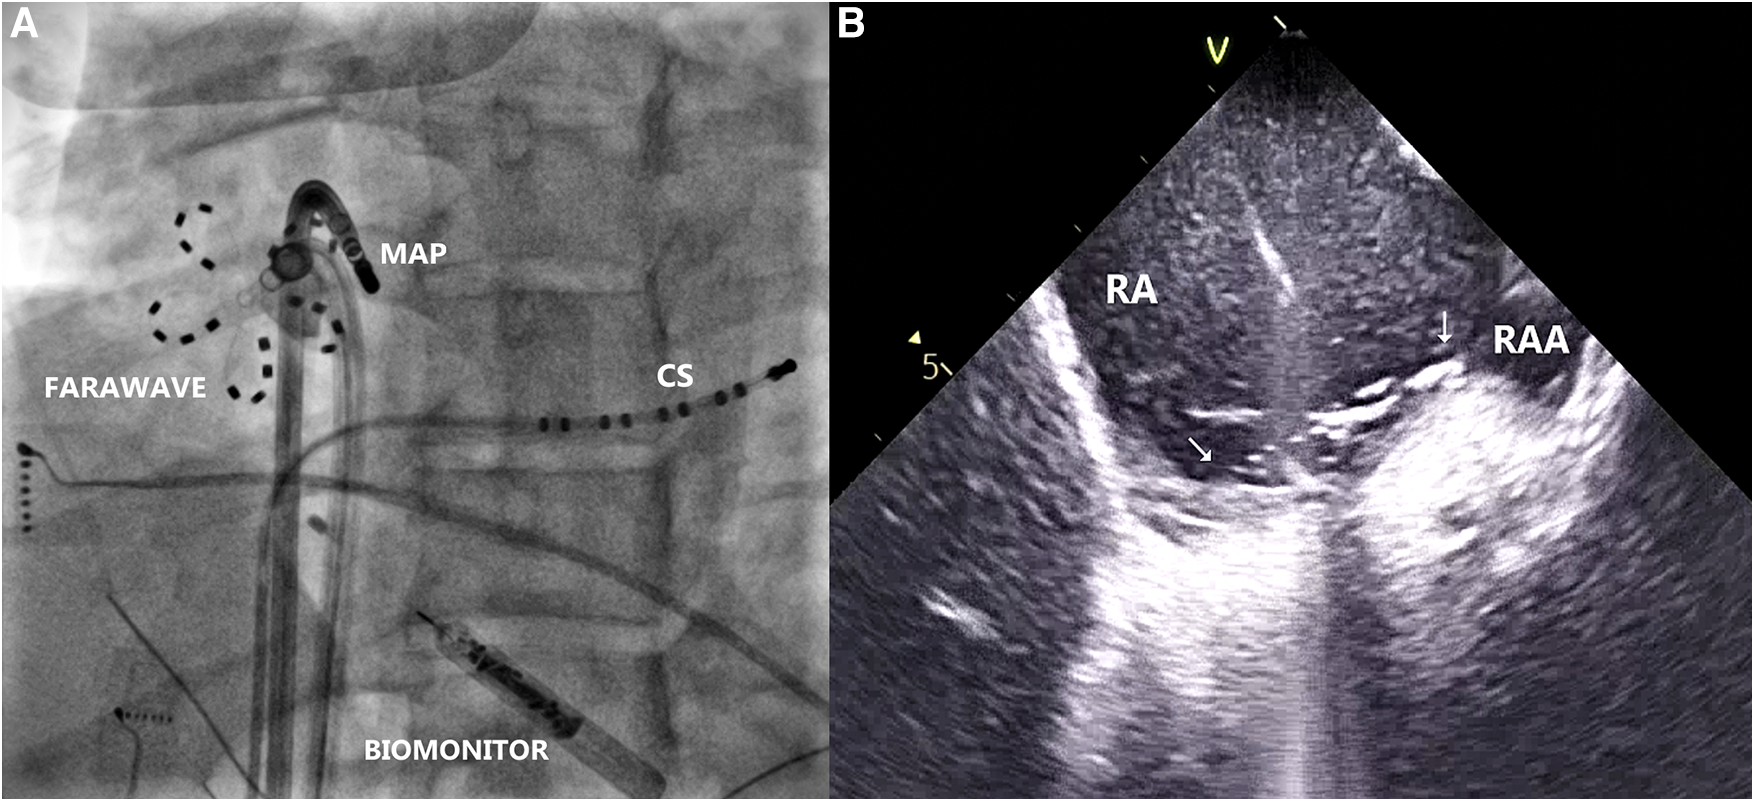

Figure 3

(A) Radiogram in left anterior oblique projection, showing farawave catheter at the site of the earliest atrial activation during ventricular pacing, parallel to mapping catheter (MAP). Decapolar catheter is introduced in the coronary sinus (CS). Biomonitor is visible in lower part of the image. (B) Intracardiac echocardiogram depicting location of the Farawave catheter and its contact with the tissue at the ablation site (arrows). RA, right atrium; RAA, right atrial appendage.